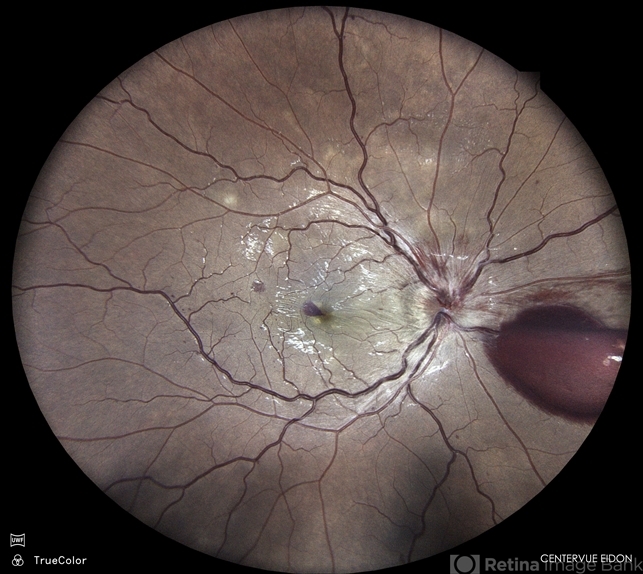

- SHH, Disc Edema, cystoid macular edema (CME)

- Color fundus photograph of a 31 year old male patient with venous stasis retinopathy.